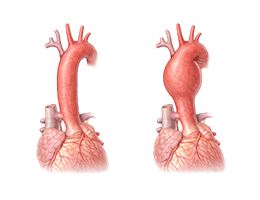

대동맥류(흉부) (Thoracic aortic aneurysm)